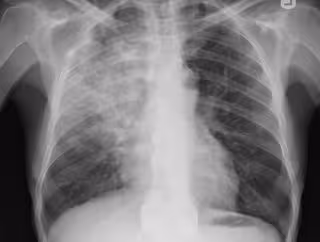

La exposición a partículas de escape de diésel puede aumentar el riesgo de sufri

La exposición a partículas de escape de diésel puede aumentar el riesgo de sufri - FLICKR/YALE ROSEN - Archivo